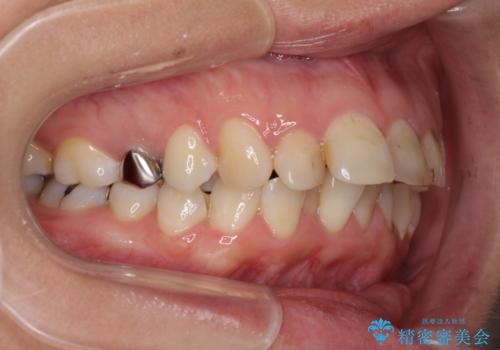

- 前歯のデコボコと前方に斜めに飛び出した前歯を気にして来院された患者様です。

口元の突出感はあまり気になっていませんでしたが、上下の前歯の前後差が大きかったため、上顎左右の第一小臼歯を抜歯し、上顎が裏側装置であるハーフリンガルにて矯正治療を行うこととしました。